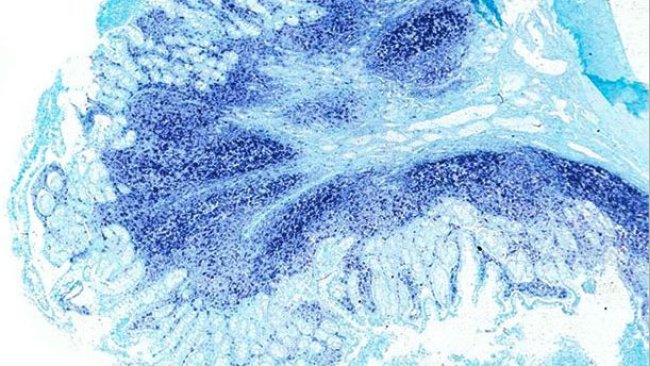

Dysenterie porcine, anciens nouveaux ennemis

Les pathologies digestives chez les porcs, qui étaient auparavant traitées individuellement contre un seul agent pathogène, constituent aujourd'hui un complexe digestif porcin auquel nous devons faire face à partir de plusieurs angles d'attaque.